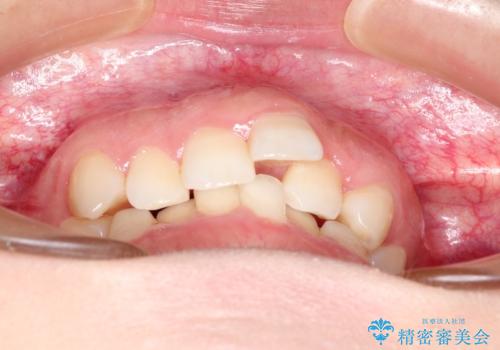

- 前歯の歯並びの改善を希望され来院された患者様です。

初診時の歯並びの状態としては、上下ともに全体に及ぶの中等度以上のがたつき(叢生)があり、全額的に歯列のアーチが内側に押しつぶされた状態でした。

強い叢生がありましたが、抜歯は行わず上下顎ともに、主に歯列弓の拡大を行い叢生を改善しました。